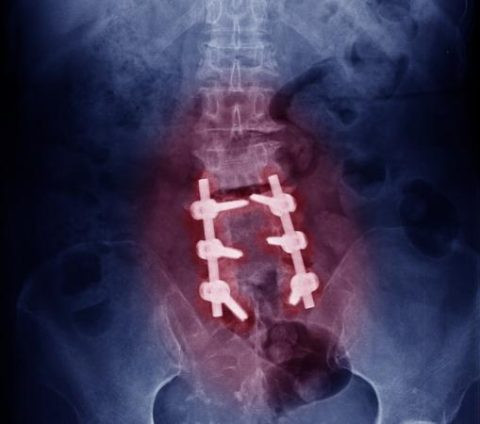

The affected vertebrae or discs are surgically removed.

A bone graft is placed to help the vertebrae fuse together.

Screws and metal rods may be inserted for stability.

Over time, the bones heal into a single solid structure.